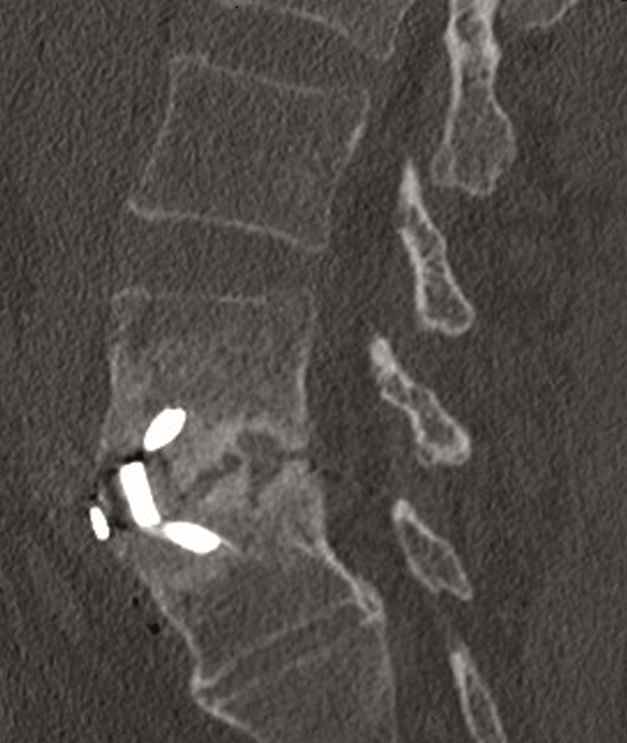

Case 5 : Degenerative scoliosis

A female patient 66-years-old with back pain, leg pain, and degenerative deformity. The x-rays show left convex degenerative scoliosis Cobb T12-L3 38. Nonoperative treatment failed. Treatment option was posterior fusion T11-L5, with URS Facet Wedge L2-L3 unilaterally.

A conventional approach for posterior correction was taken, with indirect Foraminal decompression and Facet Wedge fusion (apex curve). Facet Wedge introduction after curve correction with rod in situ. X-ray follow-up initially (Fig 20), with CT assessment of Facet Wedge fusion after 6 months (Fig 21).